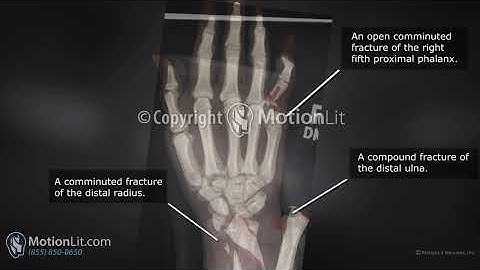

Animation Exhibits Complex Radius and Ulna ORIF Procedure